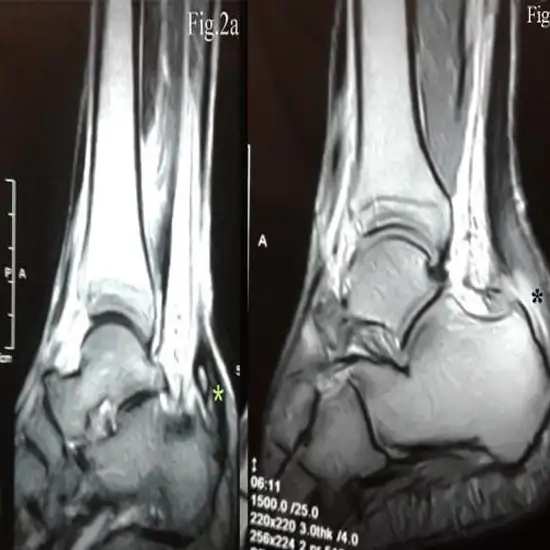

The right ankle joint's bones, tendons, ligaments, muscles, and blood vessels can be seen on an MRI.

An MRI is often used to diagnose ankle injuries. An MRI of the right ankle joint shows soft tissue lesions, like torn ligaments, tendons, and muscles, as well as broken or damaged ankle bones.